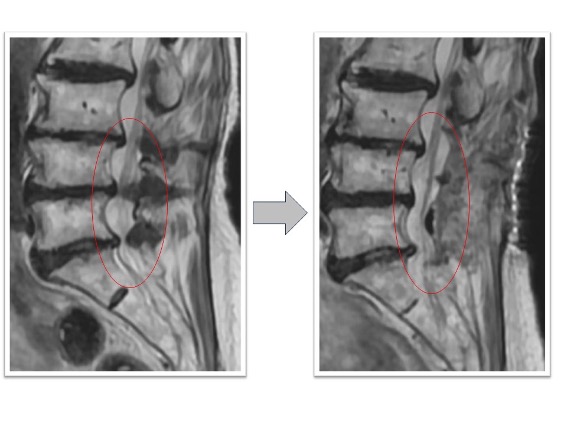

変性側弯を伴う多椎間の椎間板ヘルニア、脊柱管狭窄症(図3,4)

下肢痛、歩行障害、腰痛で来院、手術となりました。術前後のレントゲンで3椎間のOLIFによって術後側弯症が改善され、脊椎の並び(アライメント)が矯正されています(図3)。また、術前後のMRIでは施術した部位の椎間板ヘルニアおよび脊柱管狭窄がOLIFの間接除圧効果によって改善し、神経への圧迫が解除されています(図4)。術後は歩行可能、下肢痛腰痛も改善、また結果として数センチ身長が回復しています。

図3

図4